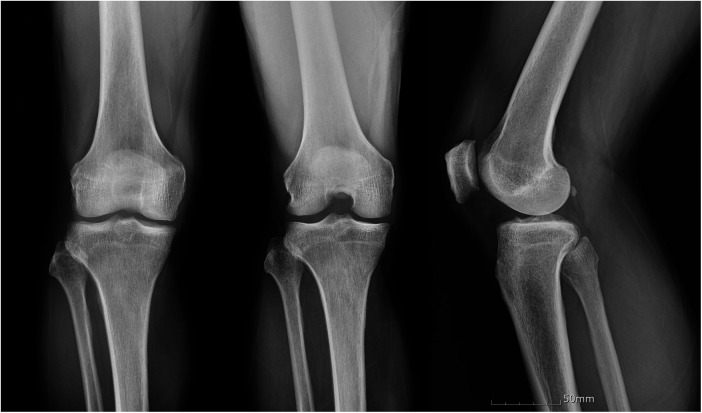

交叉韧带的黏液变性是一种罕见且常被忽视的慢性膝关节疼痛和运动受限的原因。我们报告的情况下,62岁的男子有8年的历史不适,进行性屈曲挛缩,并限制活动范围在右膝。之前在其他地方进行的两次关节镜检查未能确定原因。磁共振成像采用1.5-Tesla扫描仪,切片厚度为3mm,显示前、后交叉韧带弥漫性,韧带内信号增加,纤维完整,与“芹菜茎”征一致。关节镜检查通过标准的前外侧和前内侧门显示两个十字韧带肥大,淡黄色组织。每个韧带大约50%的体积被切除,保留了剩余的完整纤维以保持稳定性。组织学检查证实粘液变性,无炎症浸润。术后6个月,患者实现完全伸展,屈曲度提高至130°,疼痛完全缓解,无临床不稳定。本病例强调了在排除常见关节内病变的情况下,将同时发生的前交叉韧带和前交叉韧带黏液变性作为难愈性膝关节僵硬患者的潜在诊断的重要性。

Mucoid degeneration of the cruciate ligaments is an uncommon and often under-recognized cause of chronic knee pain and motion limitation. We report the case of a 62-year-old man with an eight-year history of discomfort, progressive flexion contracture, and restricted range of motion in the right knee. Two prior arthroscopies performed elsewhere failed to identify the cause. Magnetic resonance imaging using a 1.5-Tesla scanner with 3-mm slice thickness demonstrated diffuse, increased intraligamentous signal with intact fibers in both the anterior and posterior cruciate ligaments, consistent with the "celery stalk" sign. Arthroscopy through standard anterolateral and anteromedial portals revealed hypertrophic, yellowish ligament tissue in both cruciates. Approximately 50% of the bulk of each ligament was resected with preservation of the remaining intact fibers to maintain stability. Histologic examination confirmed mucoid degeneration without inflammatory infiltration. At six months postoperatively, the patient achieved full extension, improved flexion to 130°, and complete resolution of pain, without clinical instability. This case emphasizes the importance of considering simultaneous ACL and PCL mucoid degeneration as a potential diagnosis in patients with refractory knee stiffness when common intra-articular pathologies have been excluded.